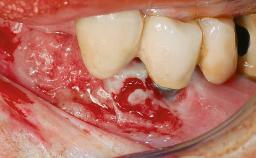

The fracture of an implant after it has been restored is one of the most severe complications. It most frequently occurs in partially edentulous jaws (1.5%). Most implant fractures involve implants with a diameter of 3.75 mm made of commercially pure titanium (Eckert 2010). Unfortunately, many cases are not reported or documented by the clinicians involved in resolving the problems created by the fracture. This case report describes the management of an implant fracture at site 36 in a middle-aged male patient. The implant had been restored with a screw-retained metal-ceramic crown.